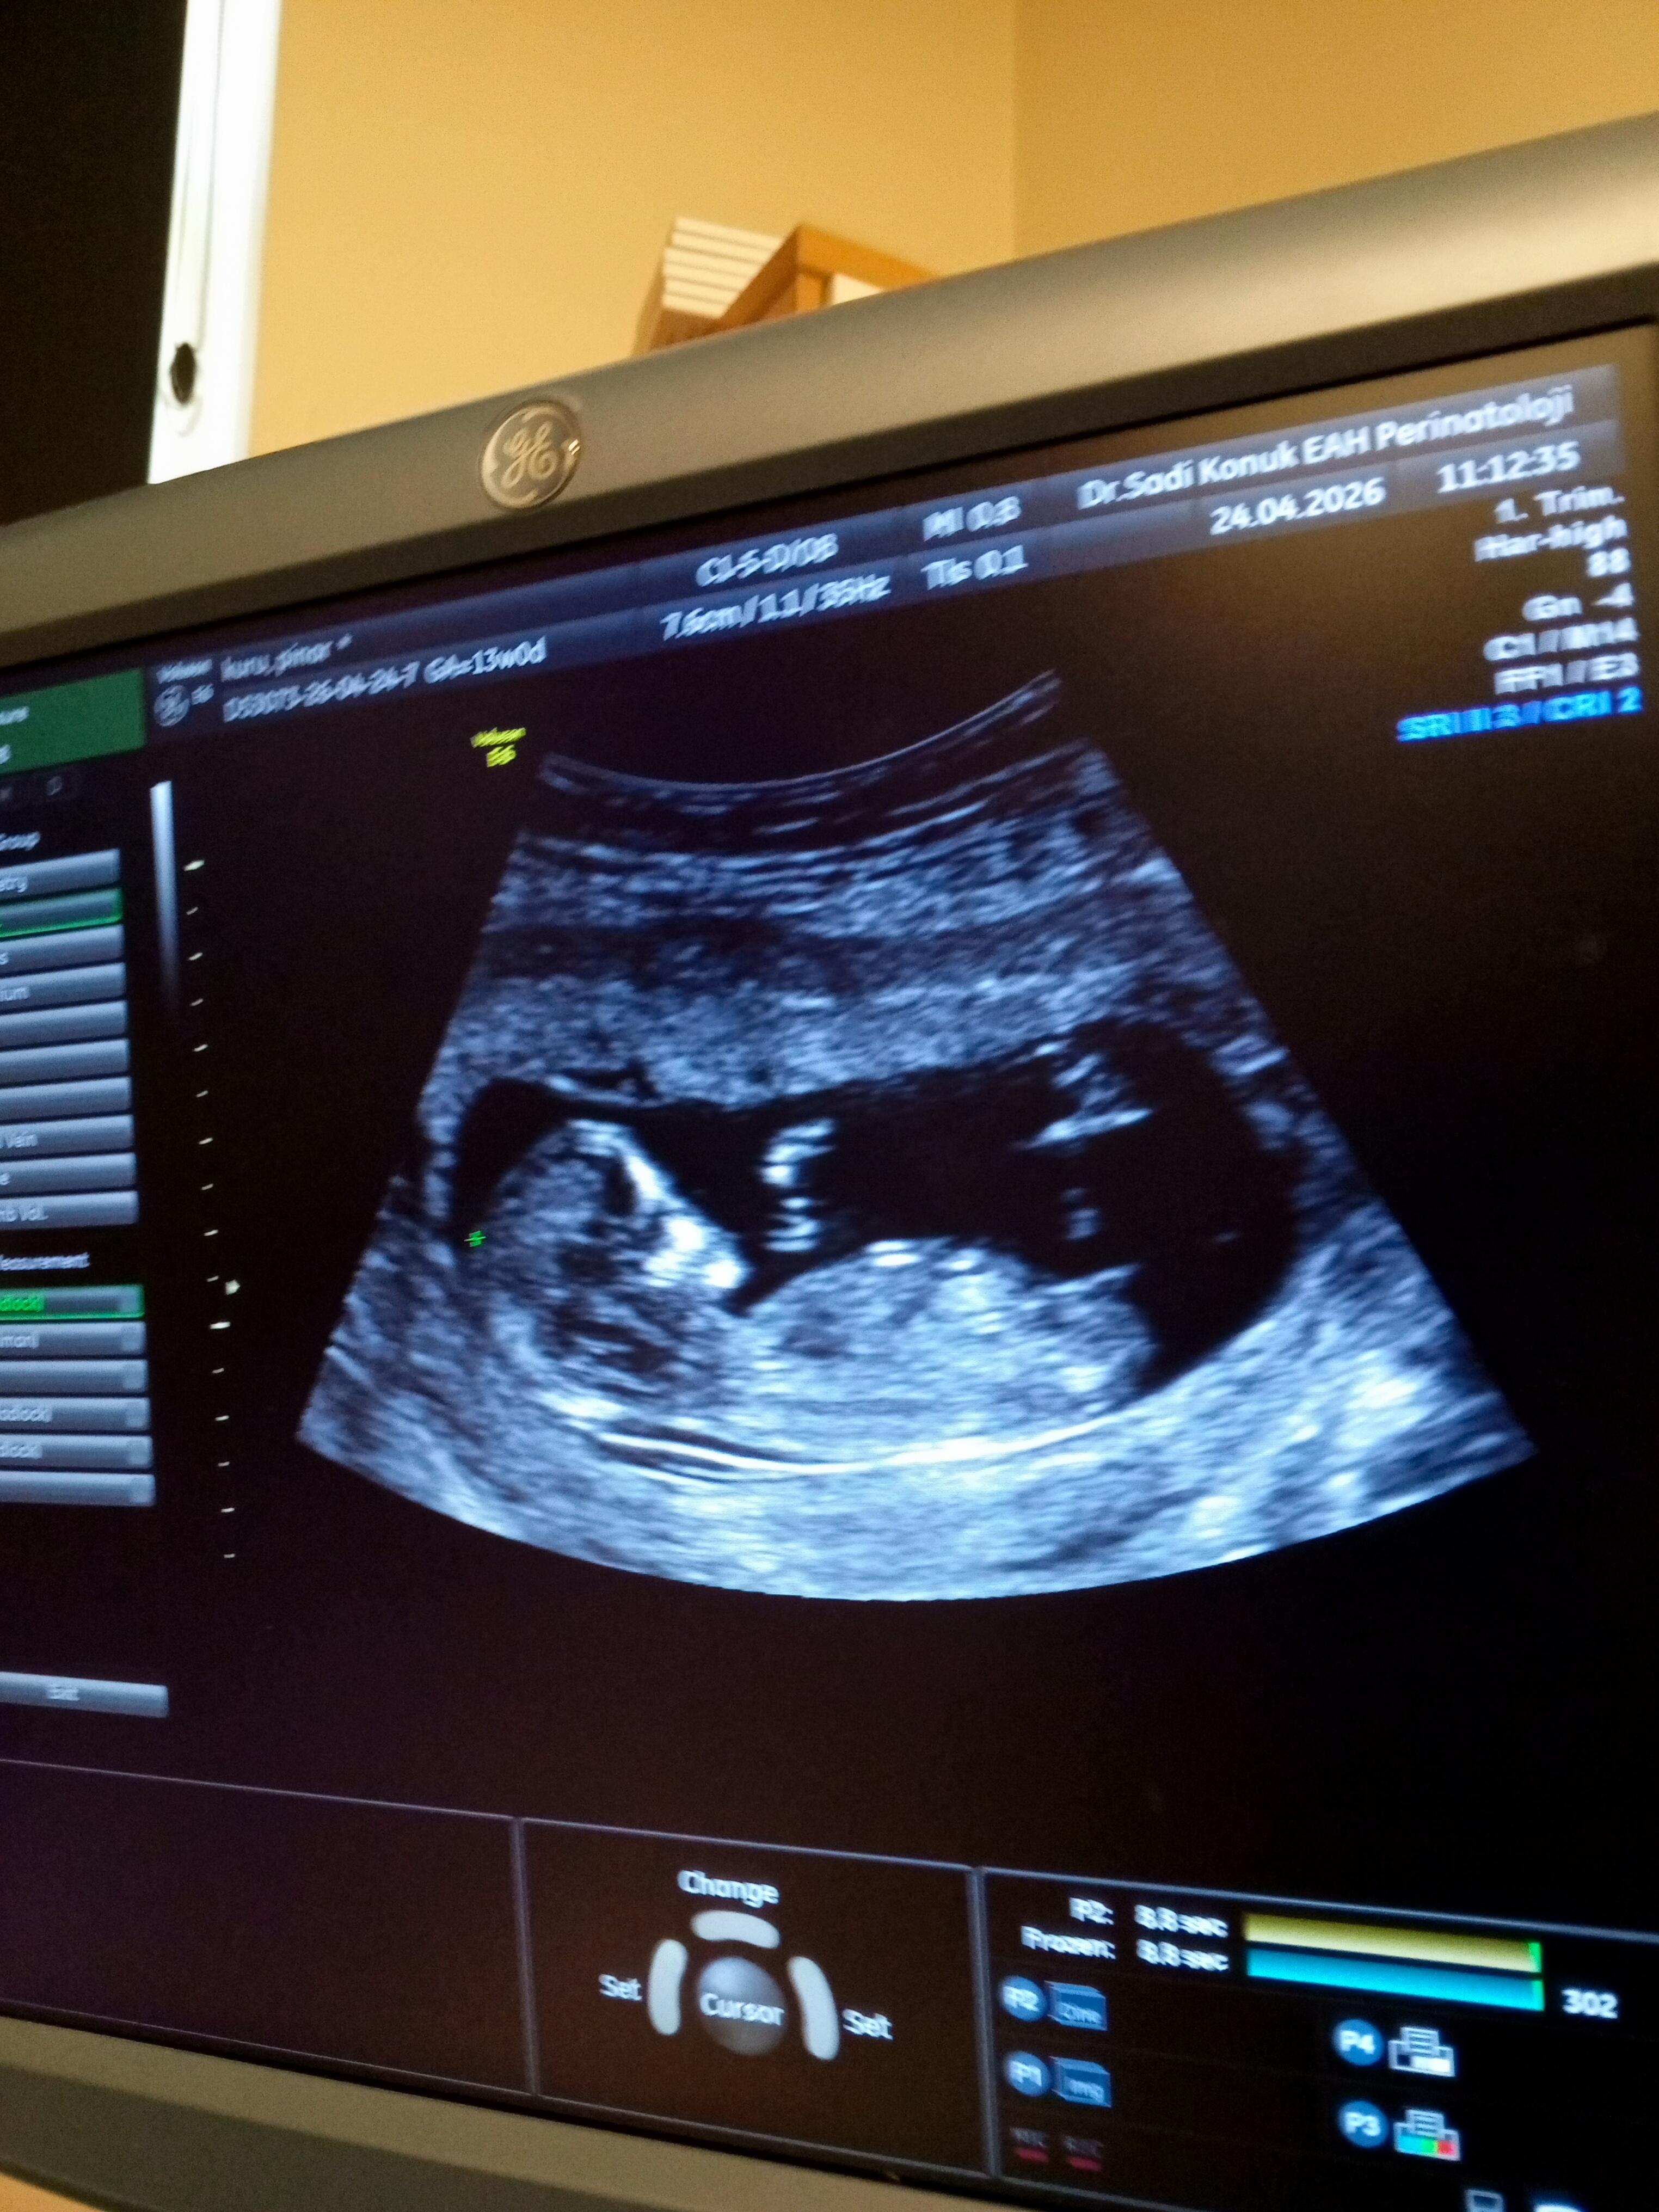

Bu attığımda yeni onada bi bakarmısın cnmm

Kızzz olabiliiir

Bu bir prenses gibi duruyor canim